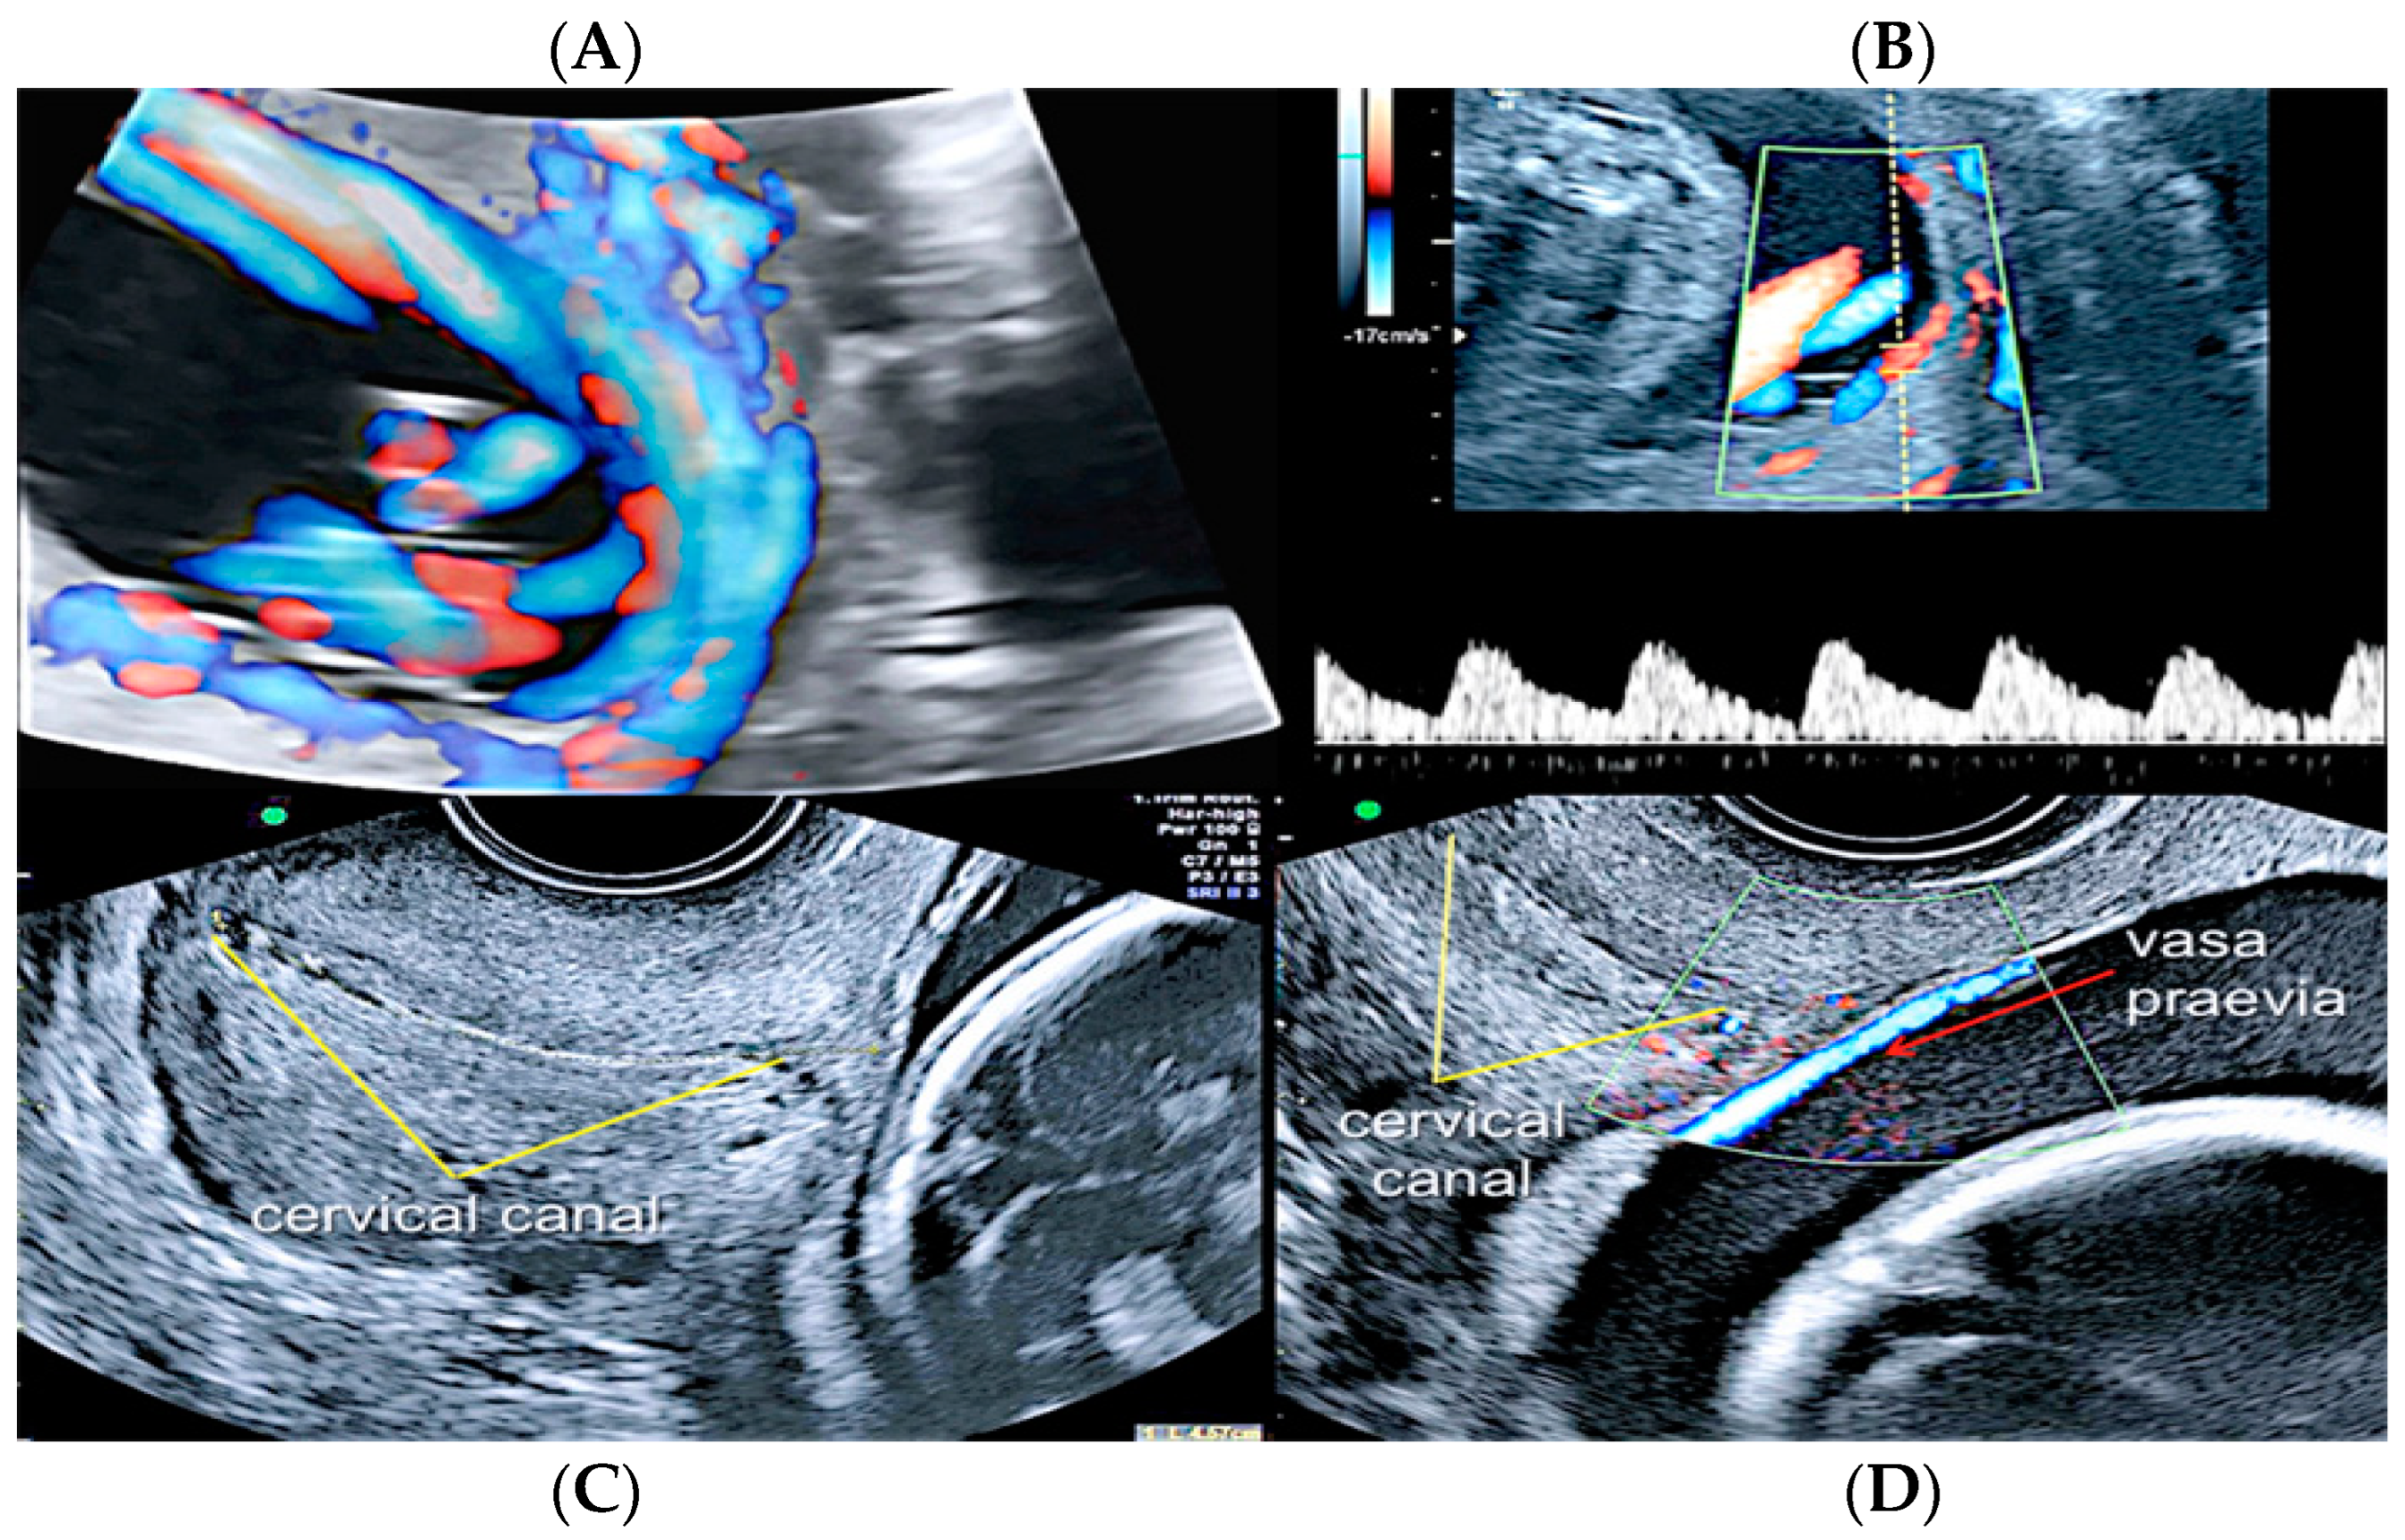

3.2.2. Vasa Praevia

3.2.3. Velamentous Umbilical Cord Insertion